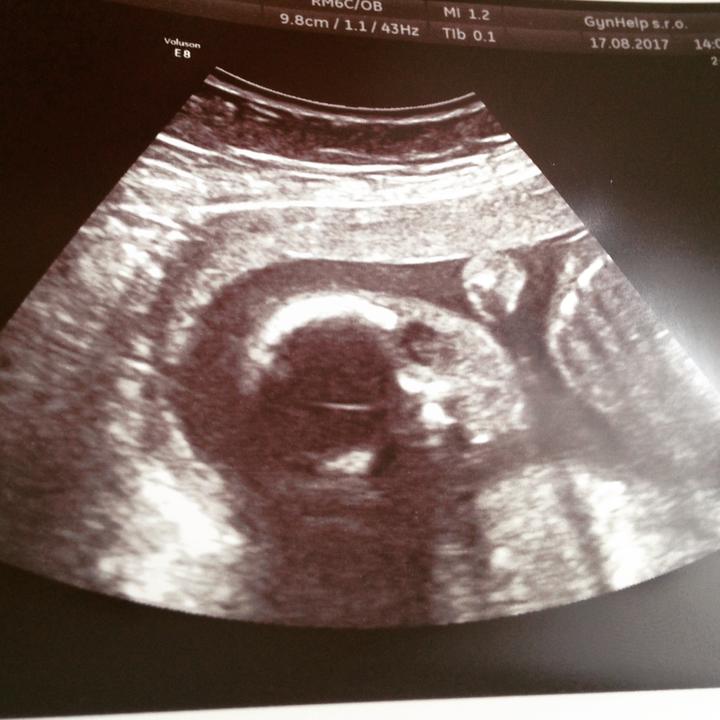

20tt. A půlka za nami 🤗🤰🏻